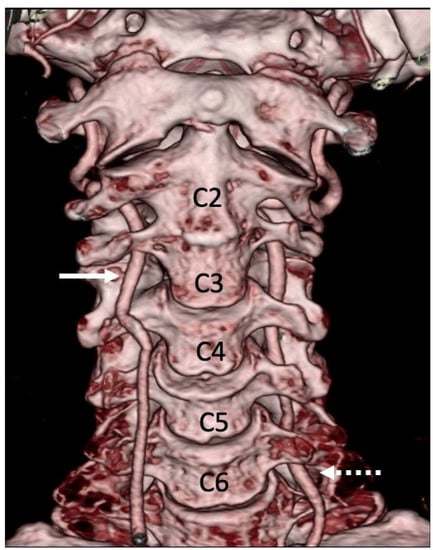

3.1. Variations in the V2 Segment

3.2. Variations of the V3 Segment